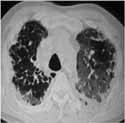

4. 13/09/02: Paciente entra en falla respiratoria en horas de la madrugada y fallece. Los resultados del TAC de Tórax fueron conocidos postmorten y algunas de las imágenes más representativas son las que siguen.

Foto 2. TACAR: Opacidades en “vidrio esmerilado”. Opacidades intralobulillares

y distorsión de la arquitectura pulmonar por fibrosis.

Foto 3. TACAR: Opacidades en “vidrio esmerilado” con bronquiectasias de tracción.

Patrón de “panal de abejas”.